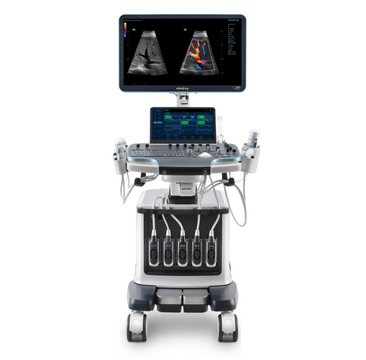

Mindray Ultrasound Machines

Ultrasound is a game-changing solution as the healthcare industry faces pressure to improve patient outcomes and reduce costs. MindrayŌĆÖs cutting-edge ultrasound machines offer a more cost-effective, real-time, and patient-friendly imaging alternative, with innovative technologies that can help improve patient outcomes and reduce costs. Explore our range of ultrasound machines, tailored to meet the needs of various medical departments.

Our Cutting-Edge Technology Evolves to Meet Healthcare Needs

MindrayŌĆÖs exclusive Living Technology? guarantee will secure your product investment by ensuring that your system remains at the cutting-edge of imaging performance excellence. Living Technology is a constantly evolving, software-based approach to providing our partners with easily upgradable enhancements made possible with our core imaging technologies: ZST+, X-Insight, and mQuadro.